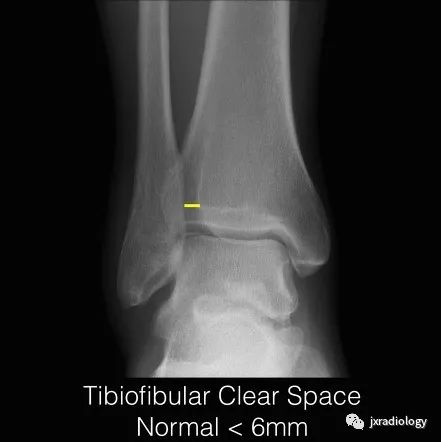

2、正常的踝关节下胫腓联合测量数据:在标准前后位X线片上胫骨远端关节面上1cm水平,下胫腓联合间隙(TFCS)>5mm或胫腓重叠(TFO)在前后位X线片上<10mm,表明存在下胫腓联合损伤。应该进行CT或MRI检查以明确诊断。

下胫腓联合间隙(tibiofibular clear space,TFCS)胫腓骨重叠(tibiofibular overlap,TFO),正常大于6mm